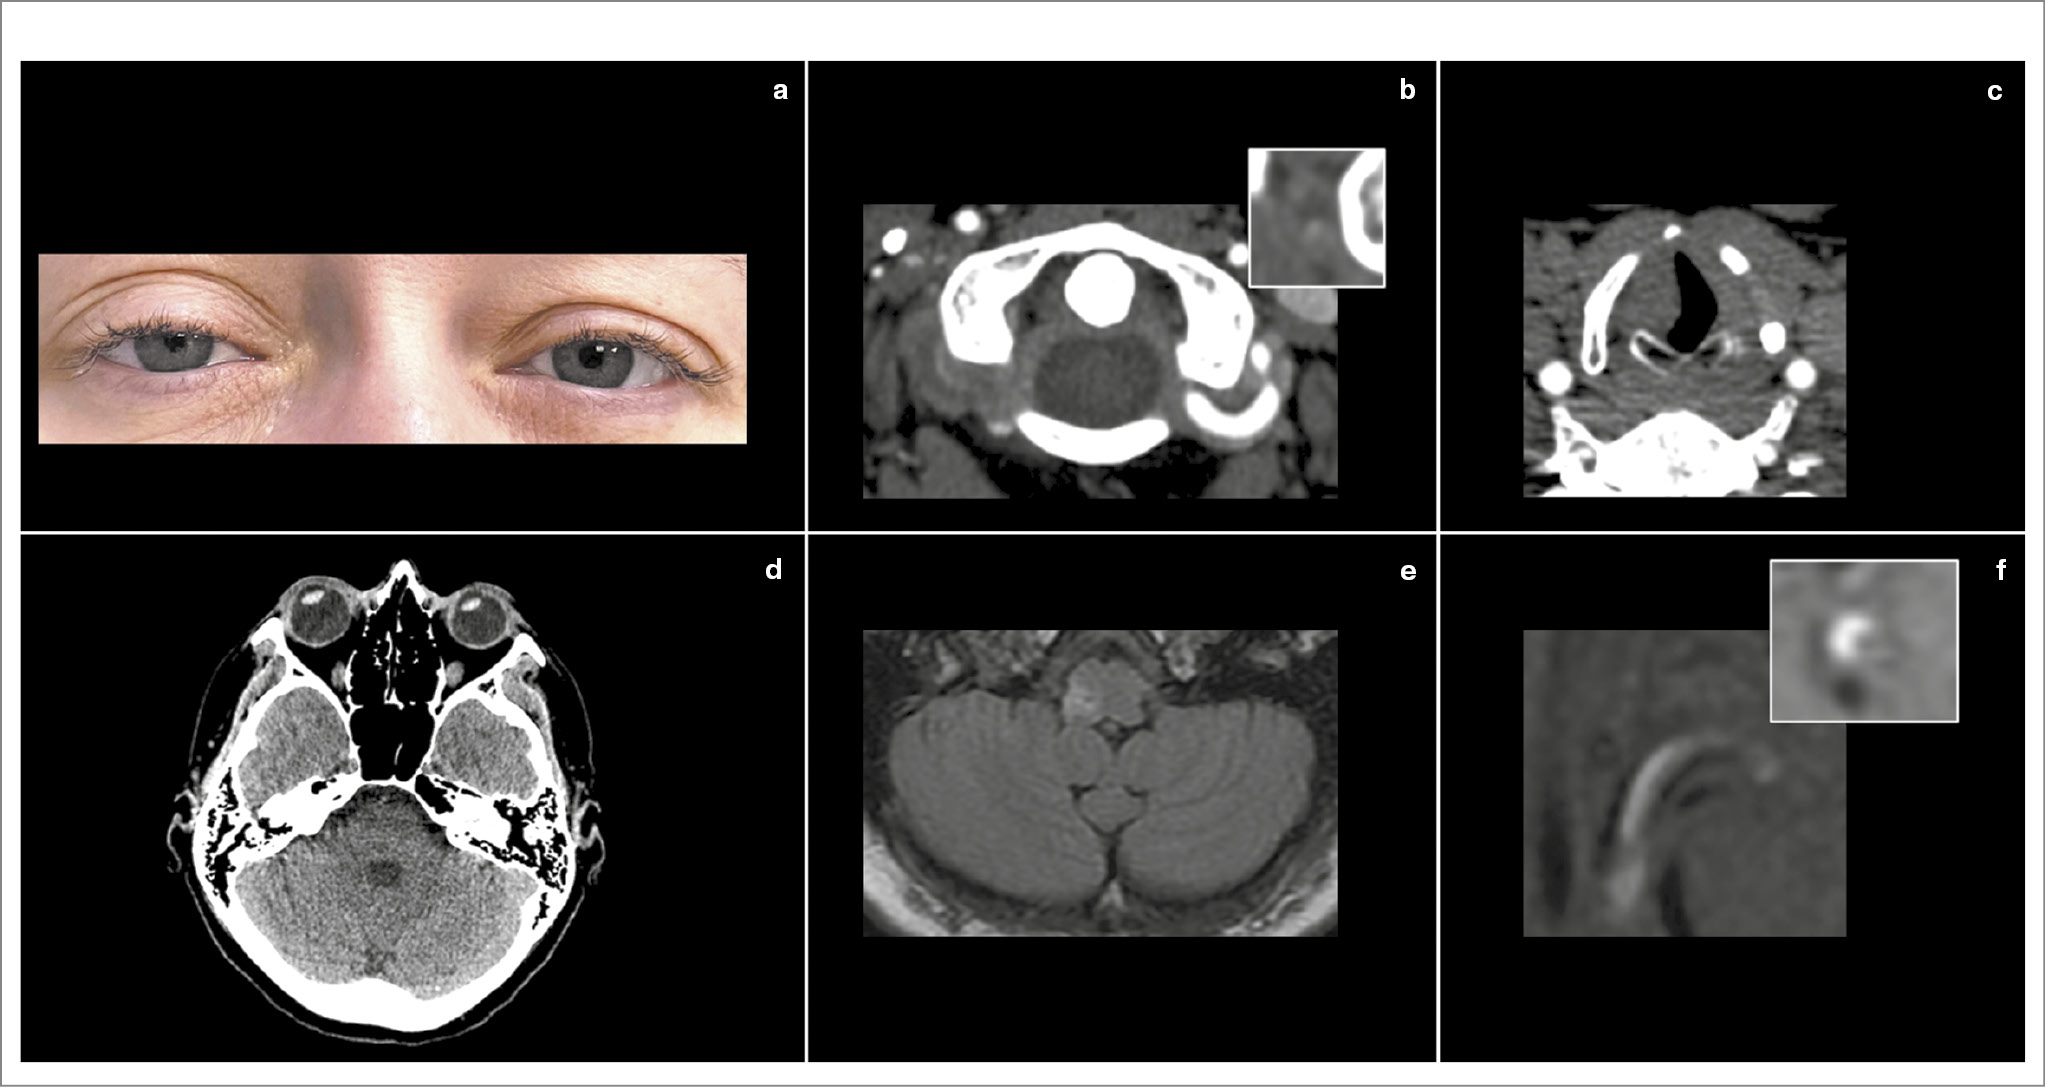

Рис. 2. ЛМИ вследствие диссекции позвоночной артерии. Пациентка 41 года. В анамнезе – синдром Вольфа–Паркинсона–Уайта, радиочастотная катетерная аблация и дефект межпредсердной перегородки по типу sinus venosus. 24 января 2024 г. после длительной поездки на автомобиле у пациентки возникли головокружение, боль в затылочной области, гнусавость голоса, онемение лица справа, снижение чувствительности и чувство жжения в левых конечностях. В течение месяца беспокоила боль в шее, за 5 дней до поступления проходила лечение у стоматолога. Поступила через 2 ч от начала заболевания. При поступлении выявлен синдром Горнера справа (a), горизонтально-торсионный нистагм, направленный влево, положительный OLD-тест справа, легкая дизартрия и дисфагия, снижение болевой и температурной (в больше степени) чувствительности в левой половине тела, выраженная туловищная атаксия. Выполнена КТ головного мозга, выявлена выраженная содружественная девиация глаз вправо – RadOLD (d). При проведении КТА выявлена окклюзия III и IV сегментов правой позвоночной артерии с паттерном «скорлупа арахиса» (гиподенсивный просвет и накопление контраста стенкой горизонтального сегмента артерии); b, а также медиальное смещение правой голосовой связки, свидетельствующее о ее парезе (c). Через 3 дня дисфагия регрессировала. На 5-е сутки выполнена МРТ головного мозга, позволяющая визуализировать правосторонний дорсолатеральный медуллярный инфаркт (d) и признаки интрамуральной гематомы стенки III сегмента левой позвоночной артерии как признак диссекции (e).